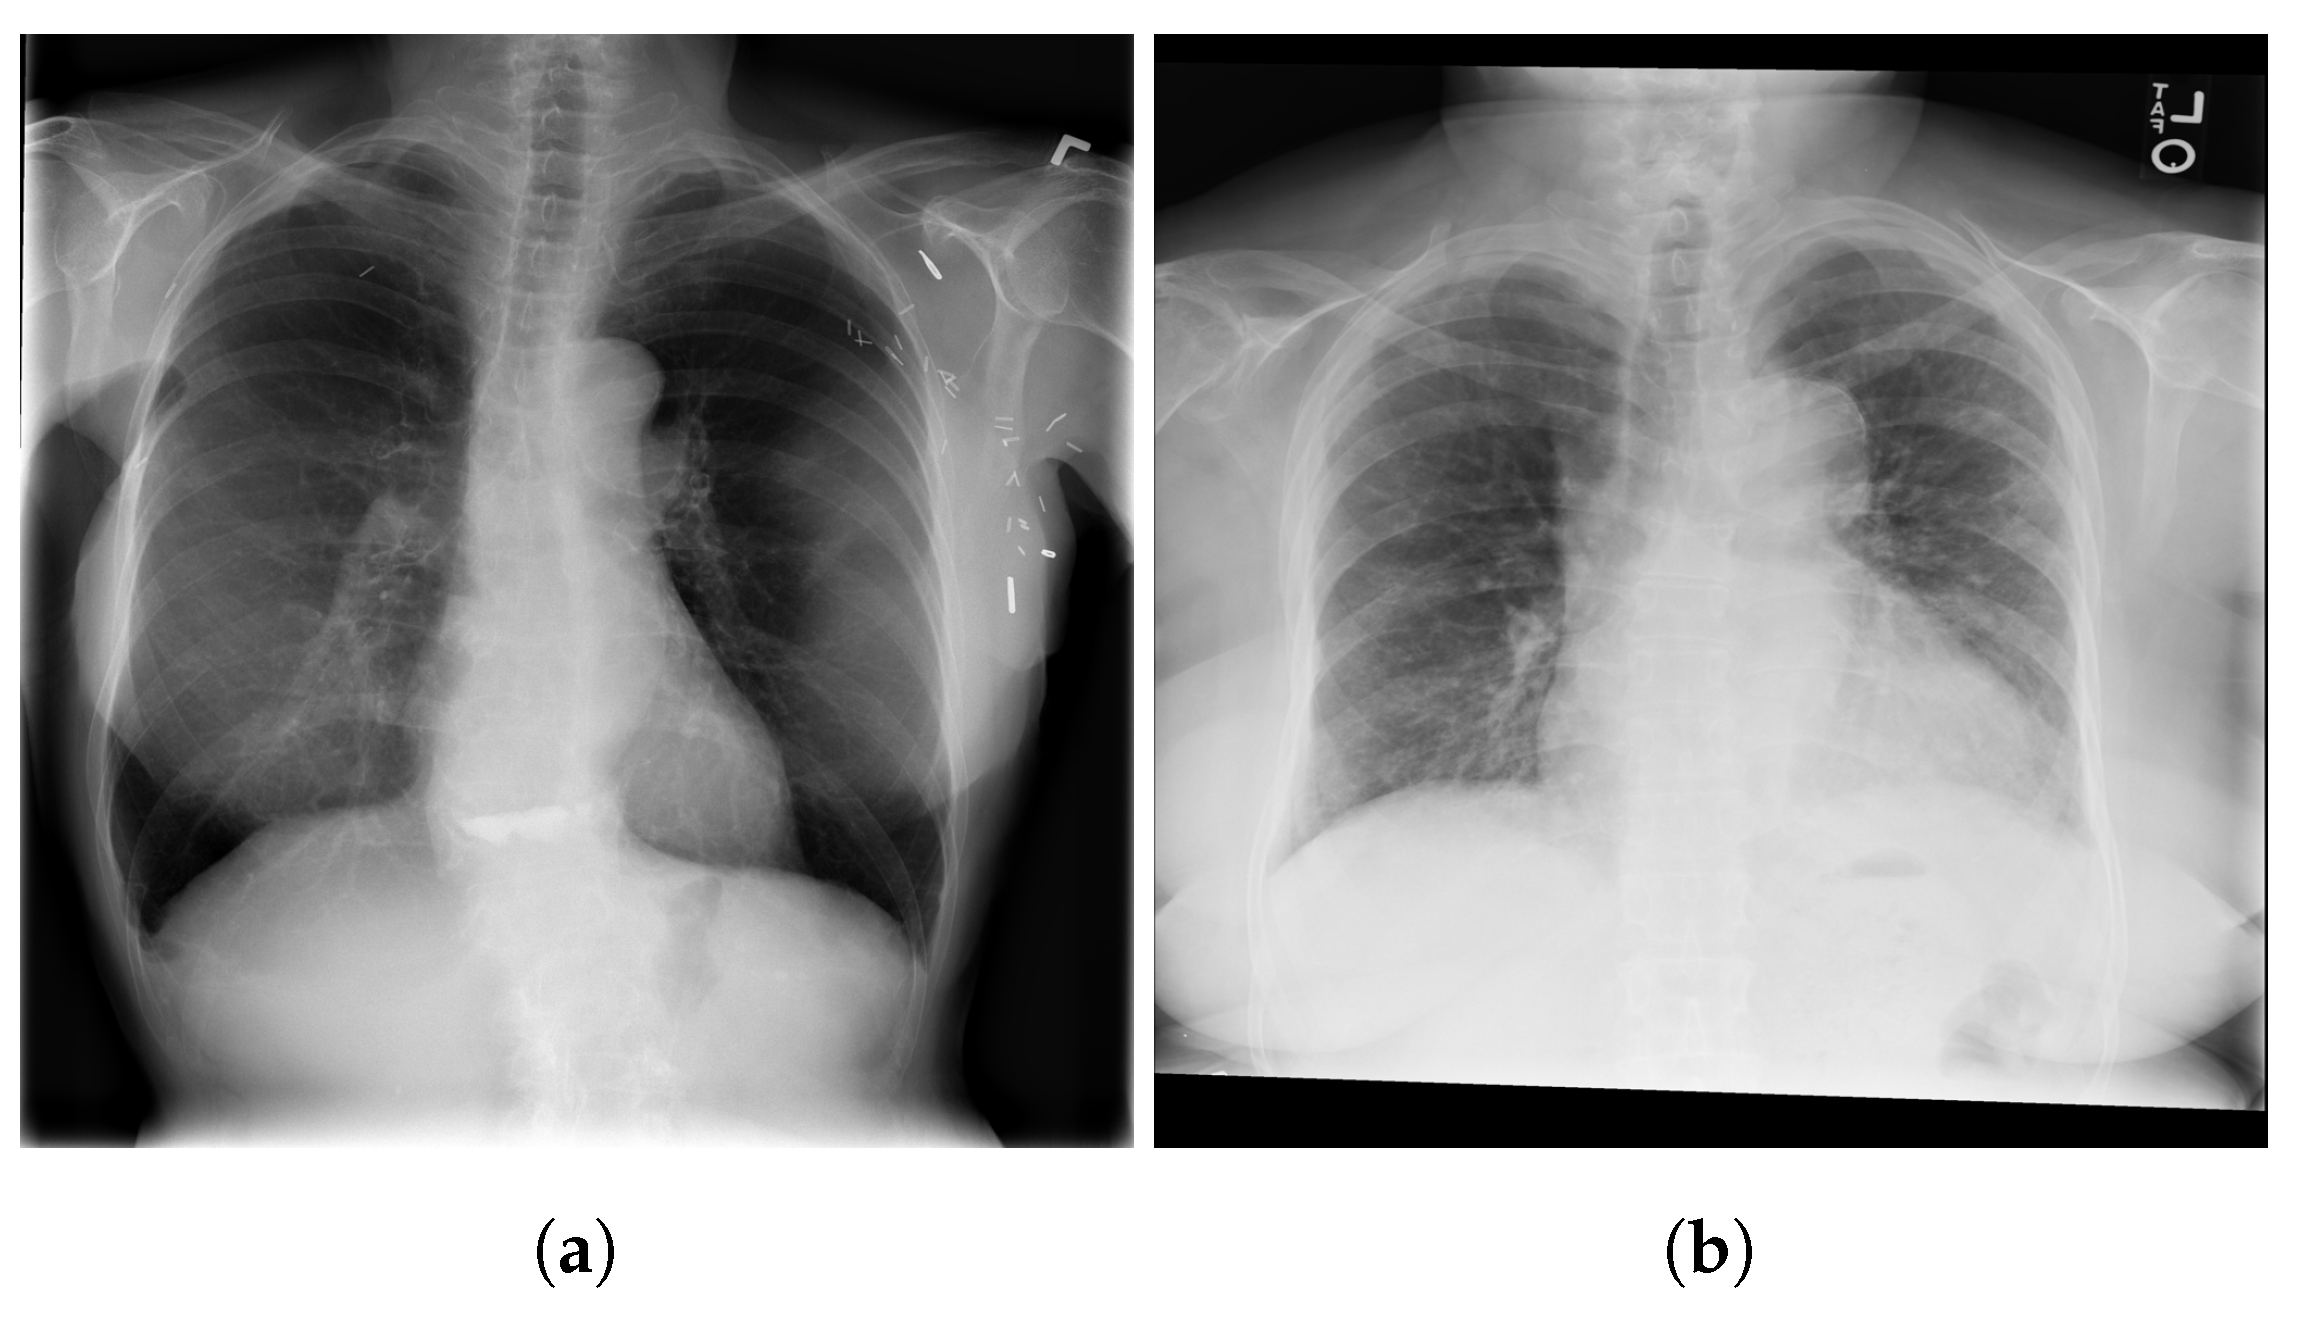

3.4.1. NIH Dataset

3.4.2. COVID-19 Image Data Collection

3.4.3. COVID-19 Radiography

3.4.4. BIMCV COVID19+

3.4.5. Montfort Dataset